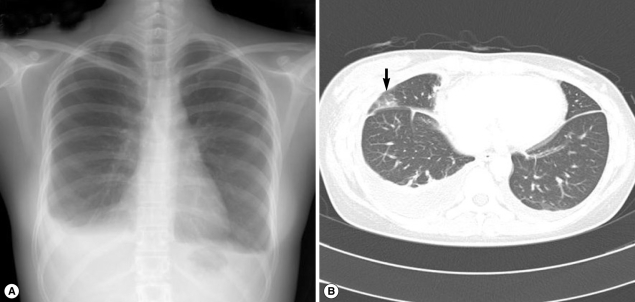

A 51-year-old woman visited our hospital to seek treatment for general myalgia and lower extremity weakness that had persisted for 1 month. She had previously undergone magnetic resonance imaging (MRI) examinations of her cervical and lumbar spines to determine the cause of her lower extremity weakness; however, the results provided no clear explanation. Her chief complaints had not been resolved by traditional rehabilitation therapy. She had eaten Kejang together with her family a few weeks before. Her past medical history and social history was uneventful. An auscultation examination revealed a normal cardiac sound, but decreased breathing in the right lower lung zone. Otherwise, a physical examination yielded no specific findings. A complete blood cell count (CBC) revealed WBC levels of 23,900/mm3, hemoglobin levels of 11.9 g/dl, platelet levels of 393,000/mm3, absolute eosinophil count (AEC) of 14,400/mm3, and erythrocyte sedimentation rate (ESR) of 74 mm/hr. The woman's chemistry battery, and electrolyte and urine analyses revealed no abnormal findings. A simple chest x-ray revealed right pleural effusion (Fig. 1A). Chest computed tomography (CT) revealed hydropneumothorax in the right hemithorax (Fig. 1B) and infiltrative lesions suggestive of parasitic infections in the liver and peritoneum. As the clinical findings were indicative of a parasitic infection, antibody test by ELISA and stool examination were performed. We could not observe parasite eggs in the stool specimen; however, the ELISA results indicated the presence of Paragonimus antibodies, even though the total serum IgE levels were 18.2 IU/ml (within normal range). The patient was treated with praziquantel (25 mg/kg, 3 times a day, for 2 days). A week after the medication, the patient's eosinophil count decreased from 14,400/mm3 to 4,250/mm3, her left pleural effusion was improved, and her chief complaints were resolved.

Fig. 1

Simple chest x-ray and computed tomography (CT) findings in case 1. (A) Pleural effusion (in the right lung) with evident fluid shifting is recognized in a lateral decubitus view. (B) Ground-glass opacity in the subpleural portion of the right lung and right hydropneumothorax (arrow).

Fig. 1 Simple chest x-ray and computed tomography (CT) findings in case 1. (A) Pleural effusion (in the right lung) with evident fluid shifting is recognized in a lateral decubitus view. (B) Ground-glass opacity in the subpleural portion of the right lung and right hydropneumothorax (arrow).